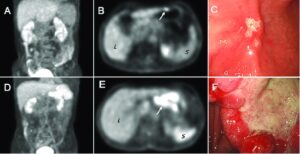

Стадия определяет расположение опухоли, ее распространенность, а также ее влияние на организм в целом. Врачам может потребоваться информация, основанная на образцах ткани, полученных при операции, поэтому определение стадии обычно продолжается до проведения всех анализов. Эта информация помогает врачу определить, какое лечение является оптимальным, спрогнозировать возможность выздоровления.

Лечение рака желудка состоит из хирургического вмешательства, радиотерапии, химиотерапии, таргетной терапии или иммунотерапии. Варианты лечения и рекомендации зависят от нескольких факторов, включая тип и стадию рака, возможные негативные реакции организма, личные предпочтения, наличие хронической патологии. Для лечения онкологии чаще всего рекомендуется комбинация разных методик. Лечение опухоли может усложняться в связи с тем, что ее часто обнаруживают только на последних стадиях.

При раке на очень ранней стадии (T1a) некоторые врачи могут порекомендовать нехирургическое лечение, называемое эндоскопической резекцией слизистой оболочки. При начальных стадиях (стадии 0 или I), когда рак еще находится только в желудке, хирургическое вмешательство используется для иссечения части желудка, содержащей рак, и соседних лимфоузлов. Это называется субтотальной или частичной гастрэктомией. При частичной гастрэктомии хирург сшивает небольшую часть желудка с пищеводом или тонким кишечником.

Если рак пророс в наружную стенку желудка с разрастанием в лимфатические узлы или без, можно использовать хирургическое вмешательство плюс химиотерапию или химиотерапию с радиотерапией. Хирург может выполнить субтотальную гастрэктомию или полную гастрэктомию, то есть, удаление всего желудка. При тотальной гастрэктомии хирург соединяет пищевод непосредственно с тонким кишечником.